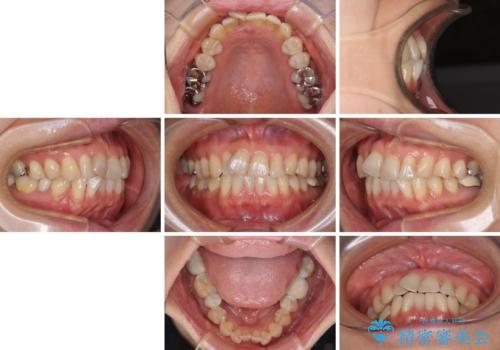

- 40代女性

- 矯正装置

- 審美装置

- 治療期間

- 1年10ヶ月

- 前歯のデコボコを気にして来院された患者様です。

インビザラインでもワイヤー装置でも対応可能であったので、両者のデメリットをご説明し、選択していただくことになりました。

マウスピース矯正の装着時間の長さや自己管理の重要性を煩わしいと感じられ、低依存で確実に治療ができるワイヤー矯正を選択されました。

舌突出癖により、上下前歯がなかなか接触せずに治療期間を要しましたが、舌のトレーニングにより無事に治療を終えることができました。